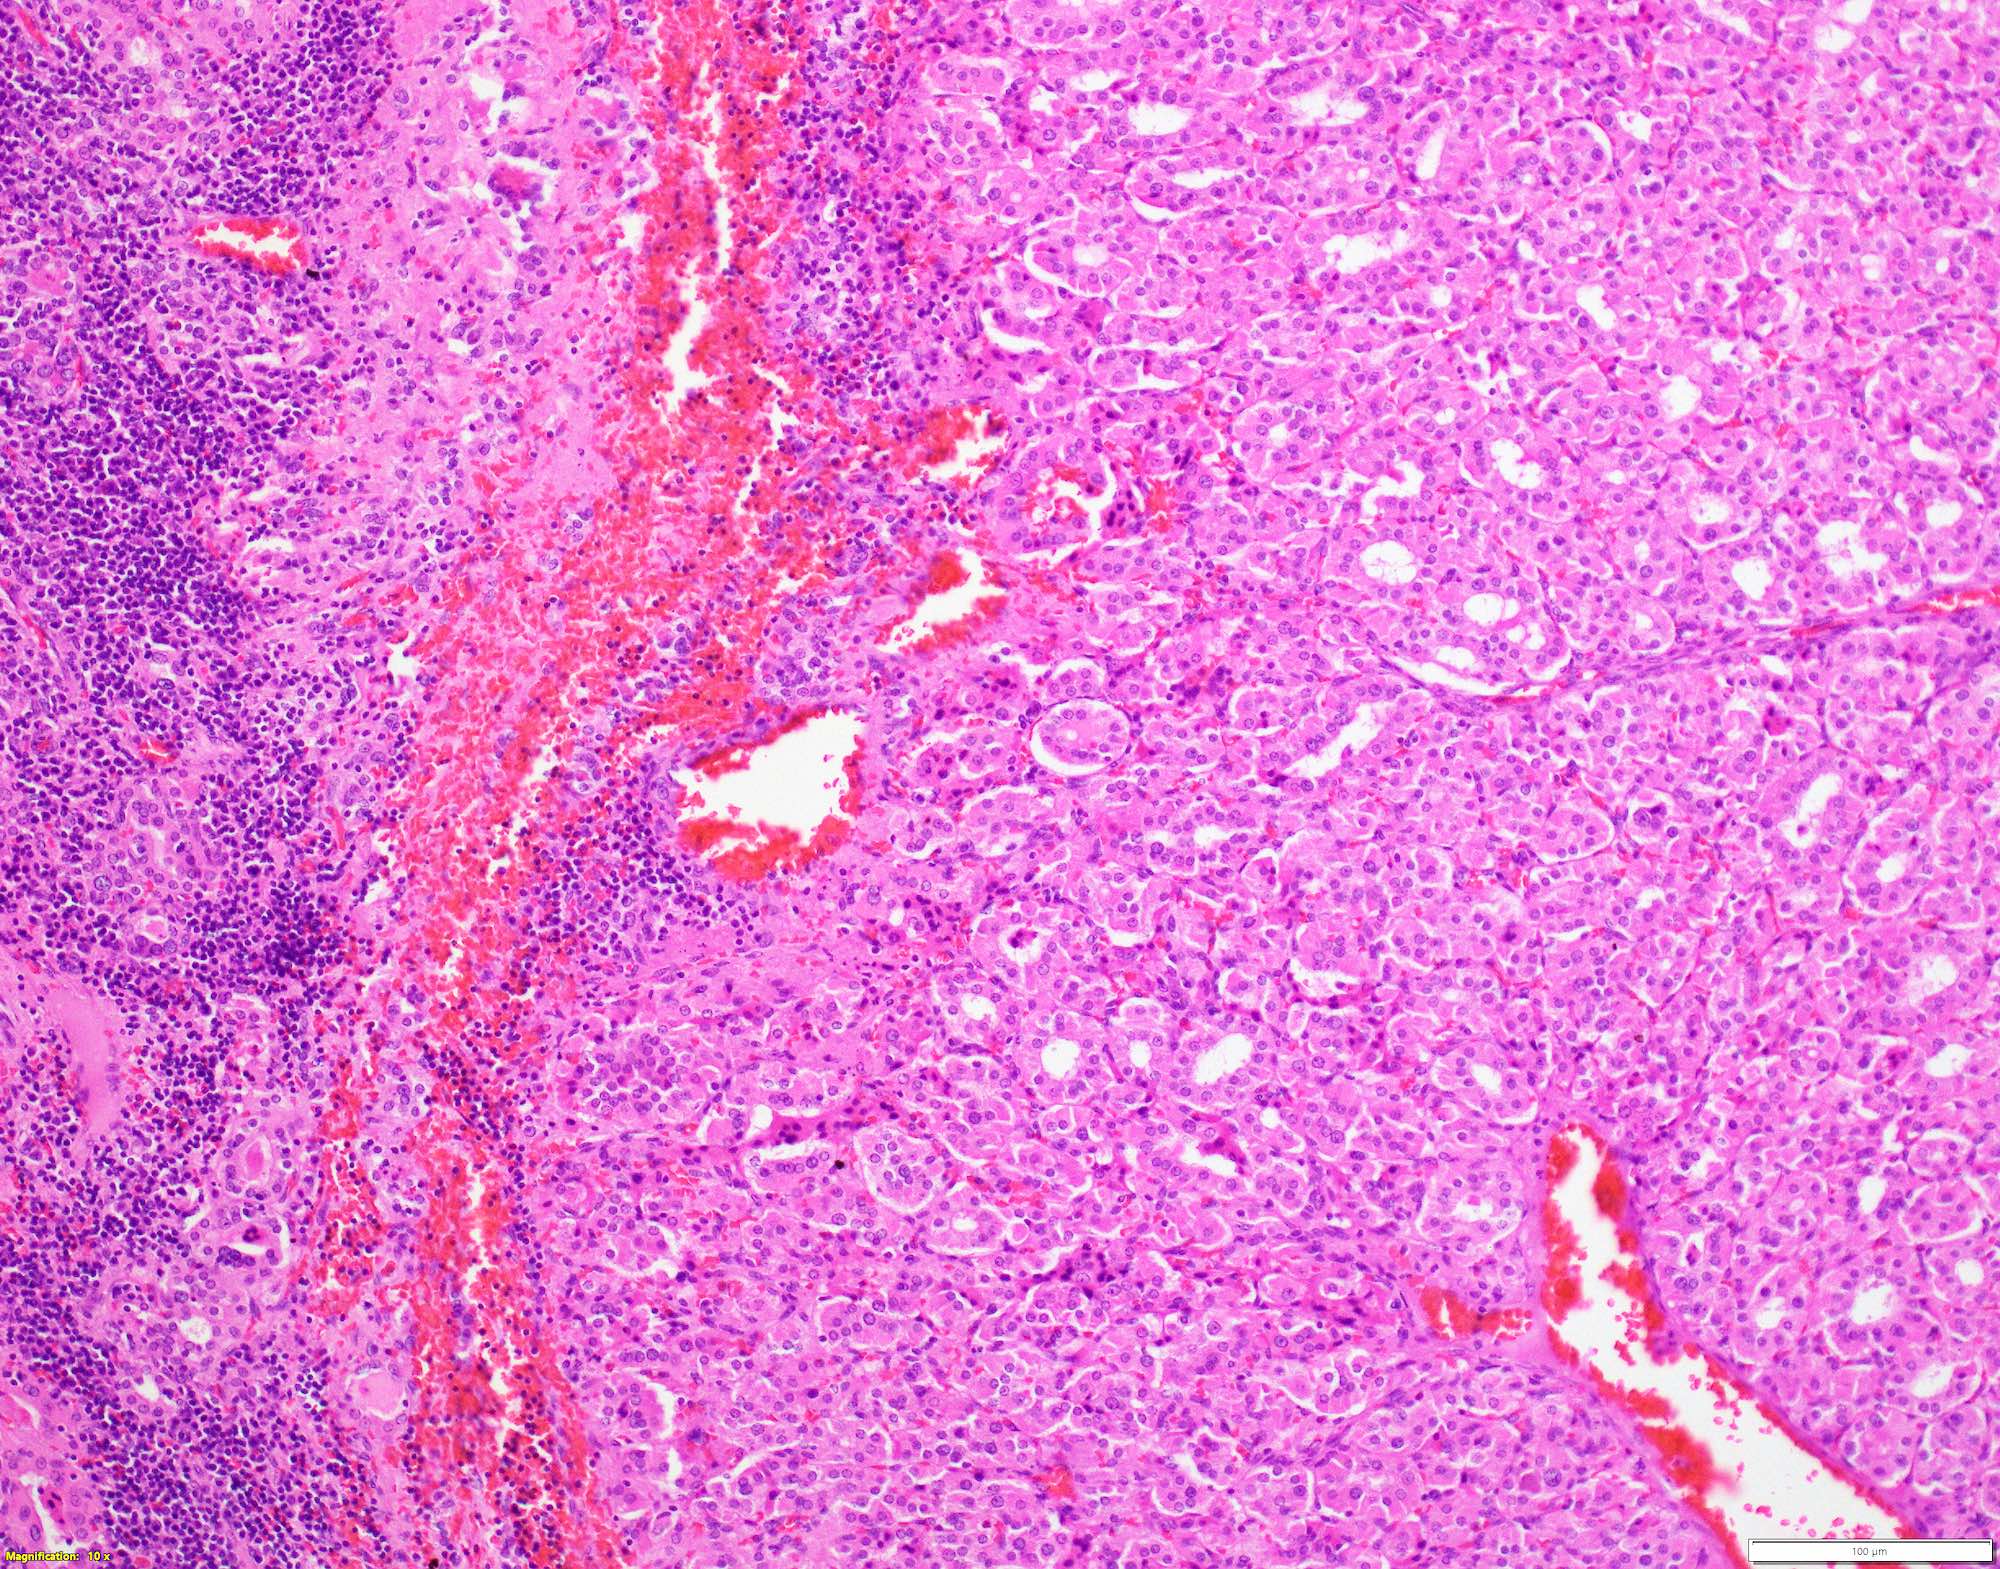

Microscopic (histologic) description

- Classic form: diffuse infiltration of thyroid parenchyma with lymphocytes and plasma cells; lymphoid follicle formation with germinal centers (Best Pract Res Clin Endocrinol Metab 2019;33:101367)

- Polymorphic lymphocytic infiltrate, predominantly T cells

- Thyroid follicular destruction

- Atrophic thyroid follicles; many lined by oncocytic cells / oncocytes having abundant granular eosinophilic cytoplasm; rarely squamous metaplasia

- Later fibrosis and nodularity (Virchows Arch 2013;462:557)

- Fibrous (or fibrosing) variant: extensive keloid-like fibrosis of thyroid parenchyma, fibrous septa divide the parenchyma into lobules, mononuclear cell infiltration, lymphoid follicles, thyroid follicular atrophy, oncocytic cell and squamous metaplasia (Autoimmun Rev 2014;13:391)

- IgG4 related variant: dense lymphoplasmacytic infiltrate, enriched in IgG4 producing plasma cells (> 20 cells per high power field); interstitial fibrosis; often associated with obliterative phlebitis (Autoimmun Rev 2014;13:391)

- Juvenile thyroiditis, Hashitoxicosis and painless thyroiditis: rare / absent germinal center formation and follicular atrophy, follicular cell hyperplasia, less pronounced oncocytic cell metaplasia and fibrosis (Autoimmun Rev 2014;13:391)

- Variable atypia of follicular cells and oncocytic cells, may mimic and act as a precursor (limited evidence) of papillary thyroid carcinoma (Endocr Pathol 2021;32:368)

- Squamous metaplasia of follicular epithelium can be confused with solid cell nests (J Clin Endocrinol Metab 2012;97:2209)

- May be associated with colloid goiter, follicular neoplasm, oncocytic cell neoplasm, papillary thyroid carcinoma and primary thyroid lymphoma (Acta Cytol 2009;53:507, Front Oncol 2017;7:53)

Microscopic (histologic) images

Contributed by Andrey Bychkov, M.D., Ph.D. and Shipra Agarwal, M.D.